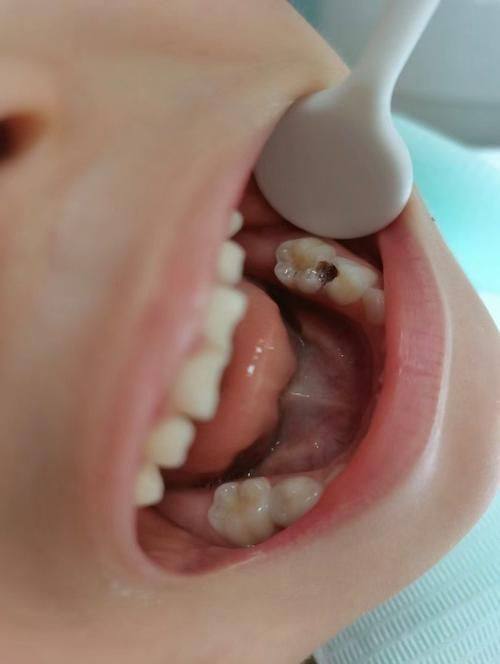

5. 我的牙齿有龋齿,来到安美齿口腔诊所补牙。医生操作特别细致,补完牙后没有任何不适,而且价格合理。这家诊所的环境也特别舒适,让人感觉特别放松,以后看牙还会选择这里。